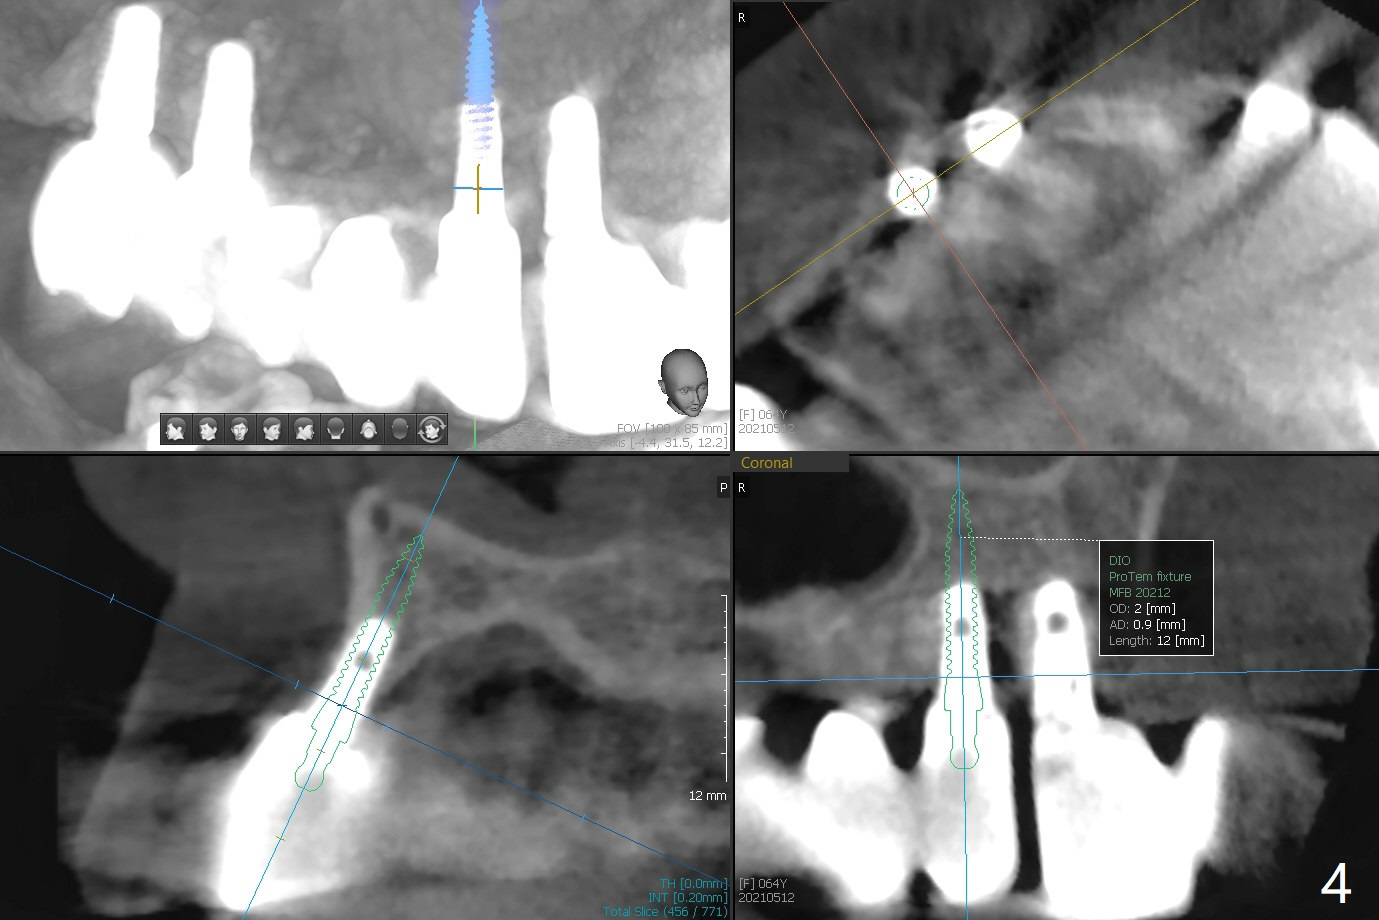

64岁女#3-7,8-13植牙桥多年,7-8之间出现间隙(图一),最近7颊侧牙龈出血,CT显示7颊侧骨板缺失(图二,三)。可能植骨有困难,似乎2x12毫米植体是解决问题部分措施(图四),接着外提升,在5,6上颌窦植骨,如果顺利,同期在6种植,2x10毫米(图五),3-5暂时改为悬臂桥,如果5提升成功,再种植一个植体。但是病人要求植骨。Return to Protect Graft 101 Xin Wei, DDS, PhD, MS 1st edition 05/12/2021, last revision 06/15/2021